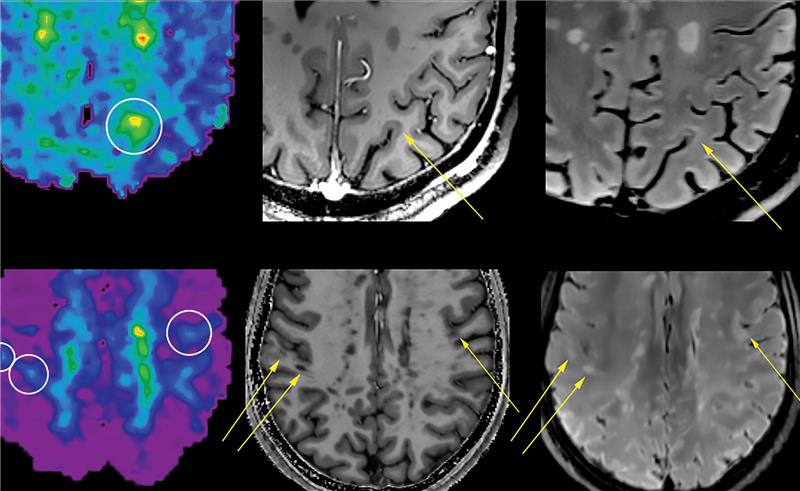

Emerging research suggests that frontotemporal atrophy on magnetic resonance imaging may be a key finding for chronic traumatic encephalopathy (CTE).